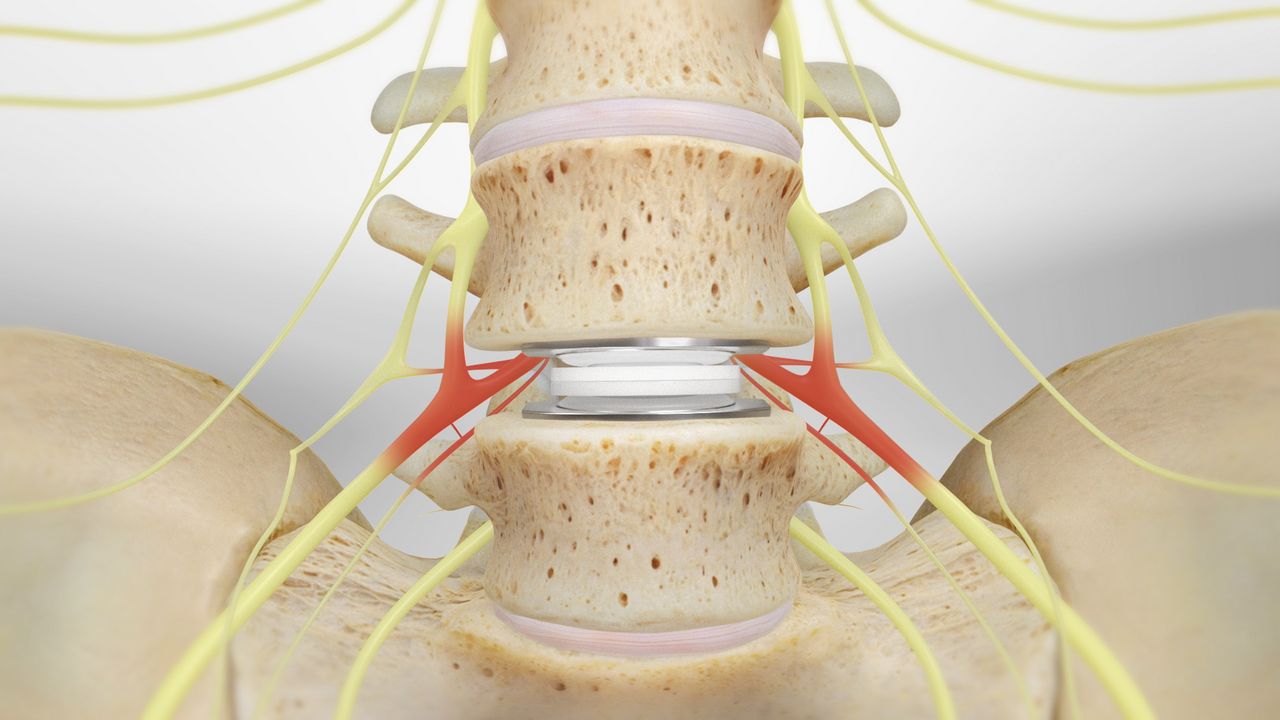

Bone grafting is a surgical procedure in which fractures or cracks in bones are repaired. This is typically done by stabilizing the broken or cracked bone using fixation materials such as surgical screws, plates, wires, or screws. The goal of this procedure is to restore the alignment of the bones and provide the necessary stability to promote proper bone healing.

A bone graft is a surgical procedure used to repair fractures or tears in bones by fixing the damaged bone pieces using plates or surgical screws, usually in the form of a patch on the bone’s surface. Bone grafts help restore bone stability, promote healing, and are used in a variety of cases that require surgical bone fixation, including:

- Structural deformity correction

- This procedure is used to correct structural deformities or bone deviations, improving appearance and function.